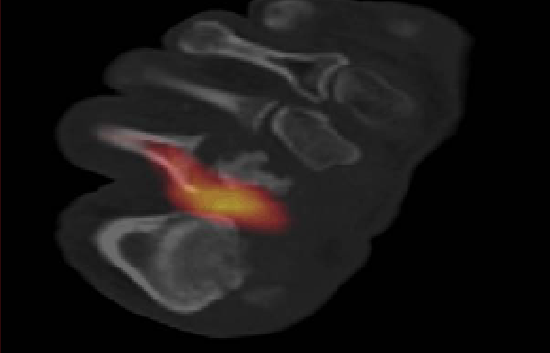

Case Study: When SPECT-CT Can Help Direct Antibiotic Therapy

This case represents an example in how this hybrid technique may be useful monitoring response to therapy. A 46-year-old male with diabetes presented to our clinic with the diagnosis of diabetic foot osteomyelitis.

He had refused surgery since the time of presentation. An infectious disease physician was involved to evaluate the patient for a long-term antibiotic regimen.

Initial Tc-99m WBC SPECT/CT demonstrated osteomyelitis of the second metatarsal head with additional involvement of the second proximal phalanx. Sequential SPECT/CT scans at two-month clinical intervals showed improvement of osteomyelitis followed by the resolution of infection after prolonged antibiotic therapy. This allowed physicians to determine when it was the proper time to stop antibiotic therapy.